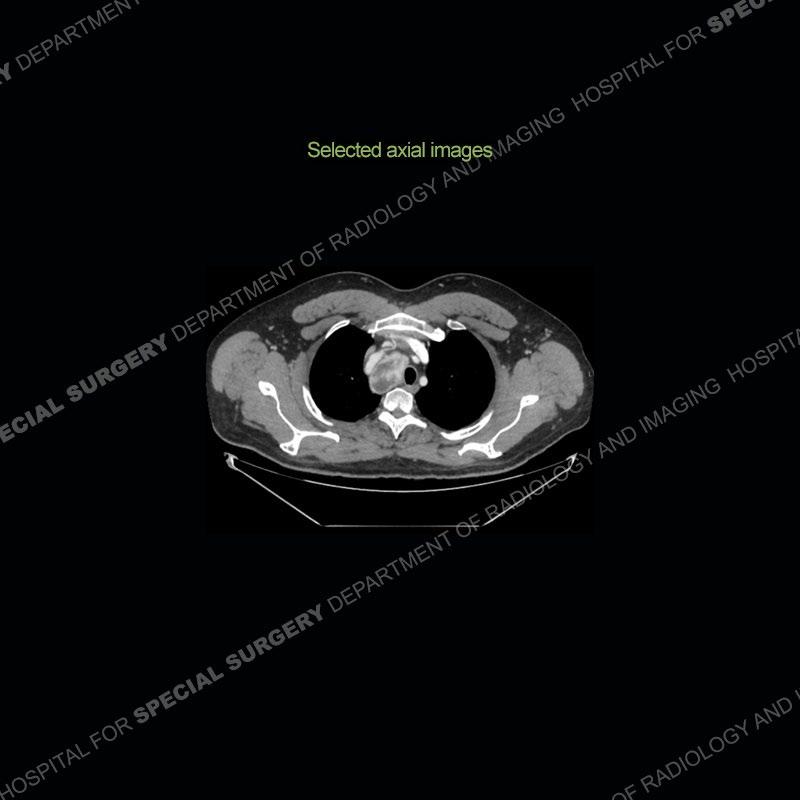

Findings

The chest radiographs demonstrate a leftward deviation of the trachea. CT images demonstrate a large, somewhat heterogeneous mass of the thyroid that extends outside the confines of the thyroid tissue. There is a subtle, enhancing soft tissue mass of the proximal right humerus. Slightly prominent mediastinal lymph nodes are present with additionally, multiple supraclavicular lymph nodes.

Although not strictly a part of the evaluation of an “incidental” thyroid lesion, evaluation of the adjacent lymph nodes and bony structures can also be quite important. In this case, there is an enhancing mass of the right humerus. This is very subtle and can only really be recognized by evaluating the density of the bone. Typicaly marrow will have a fatty density or nearly fluid density. As the density, as in this case, approaches soft tissue an infiltrative process must be entertained. Thyroid mets are markedly vascular accounting for the areas of enhancement of the humeral mass. The mediastinal and supraclavicular lymph nodes although not individually enlarged, should raise suspicion of an underlying inflammatory/neoplastic process.